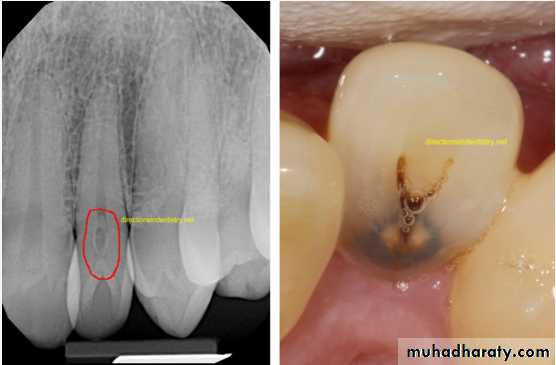

Dilacerated root. The apical portion of the root is bent buccally or lingually into the plane of the central ray. Note the halo in the apical region, produced by the PDL

space (arrow).